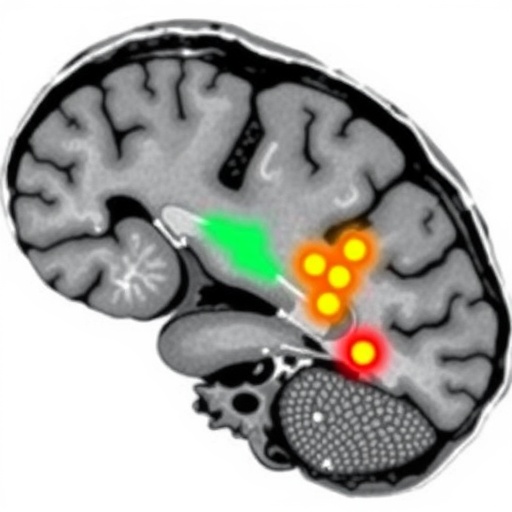

Intriguingly, the exacerbated beta-band activity observed localized predominantly to the internal segment of the globus pallidus (GPi). This structure, integral to the indirect pathway of the basal ganglia, modulates inhibitory output to motor thalamus and cortex, thereby regulating movement. The heightened beta oscillations may reflect dysfunctional inhibitory signaling within these motor circuits, precipitating the uncontrollable muscle contractions characteristic of SD. By pinpointing this electrophysiological signature, the study lays groundwork for refining neuromodulatory interventions that target these aberrant beta rhythms.

The implications of this discovery are manifold. From a clinical perspective, the ability to identify a distinct beta-band oscillation pattern during SD could enhance diagnostic precision, facilitating earlier recognition and tailored management of dystonic crises. Further, it offers a mechanistic rationale for the observed efficacy of deep brain stimulation (DBS) targeting the GPi, which is thought to disrupt pathological beta synchronization. Fine-tuning DBS parameters to specifically counteract beta-band activity might improve outcomes in patients resistant to pharmacological therapies.